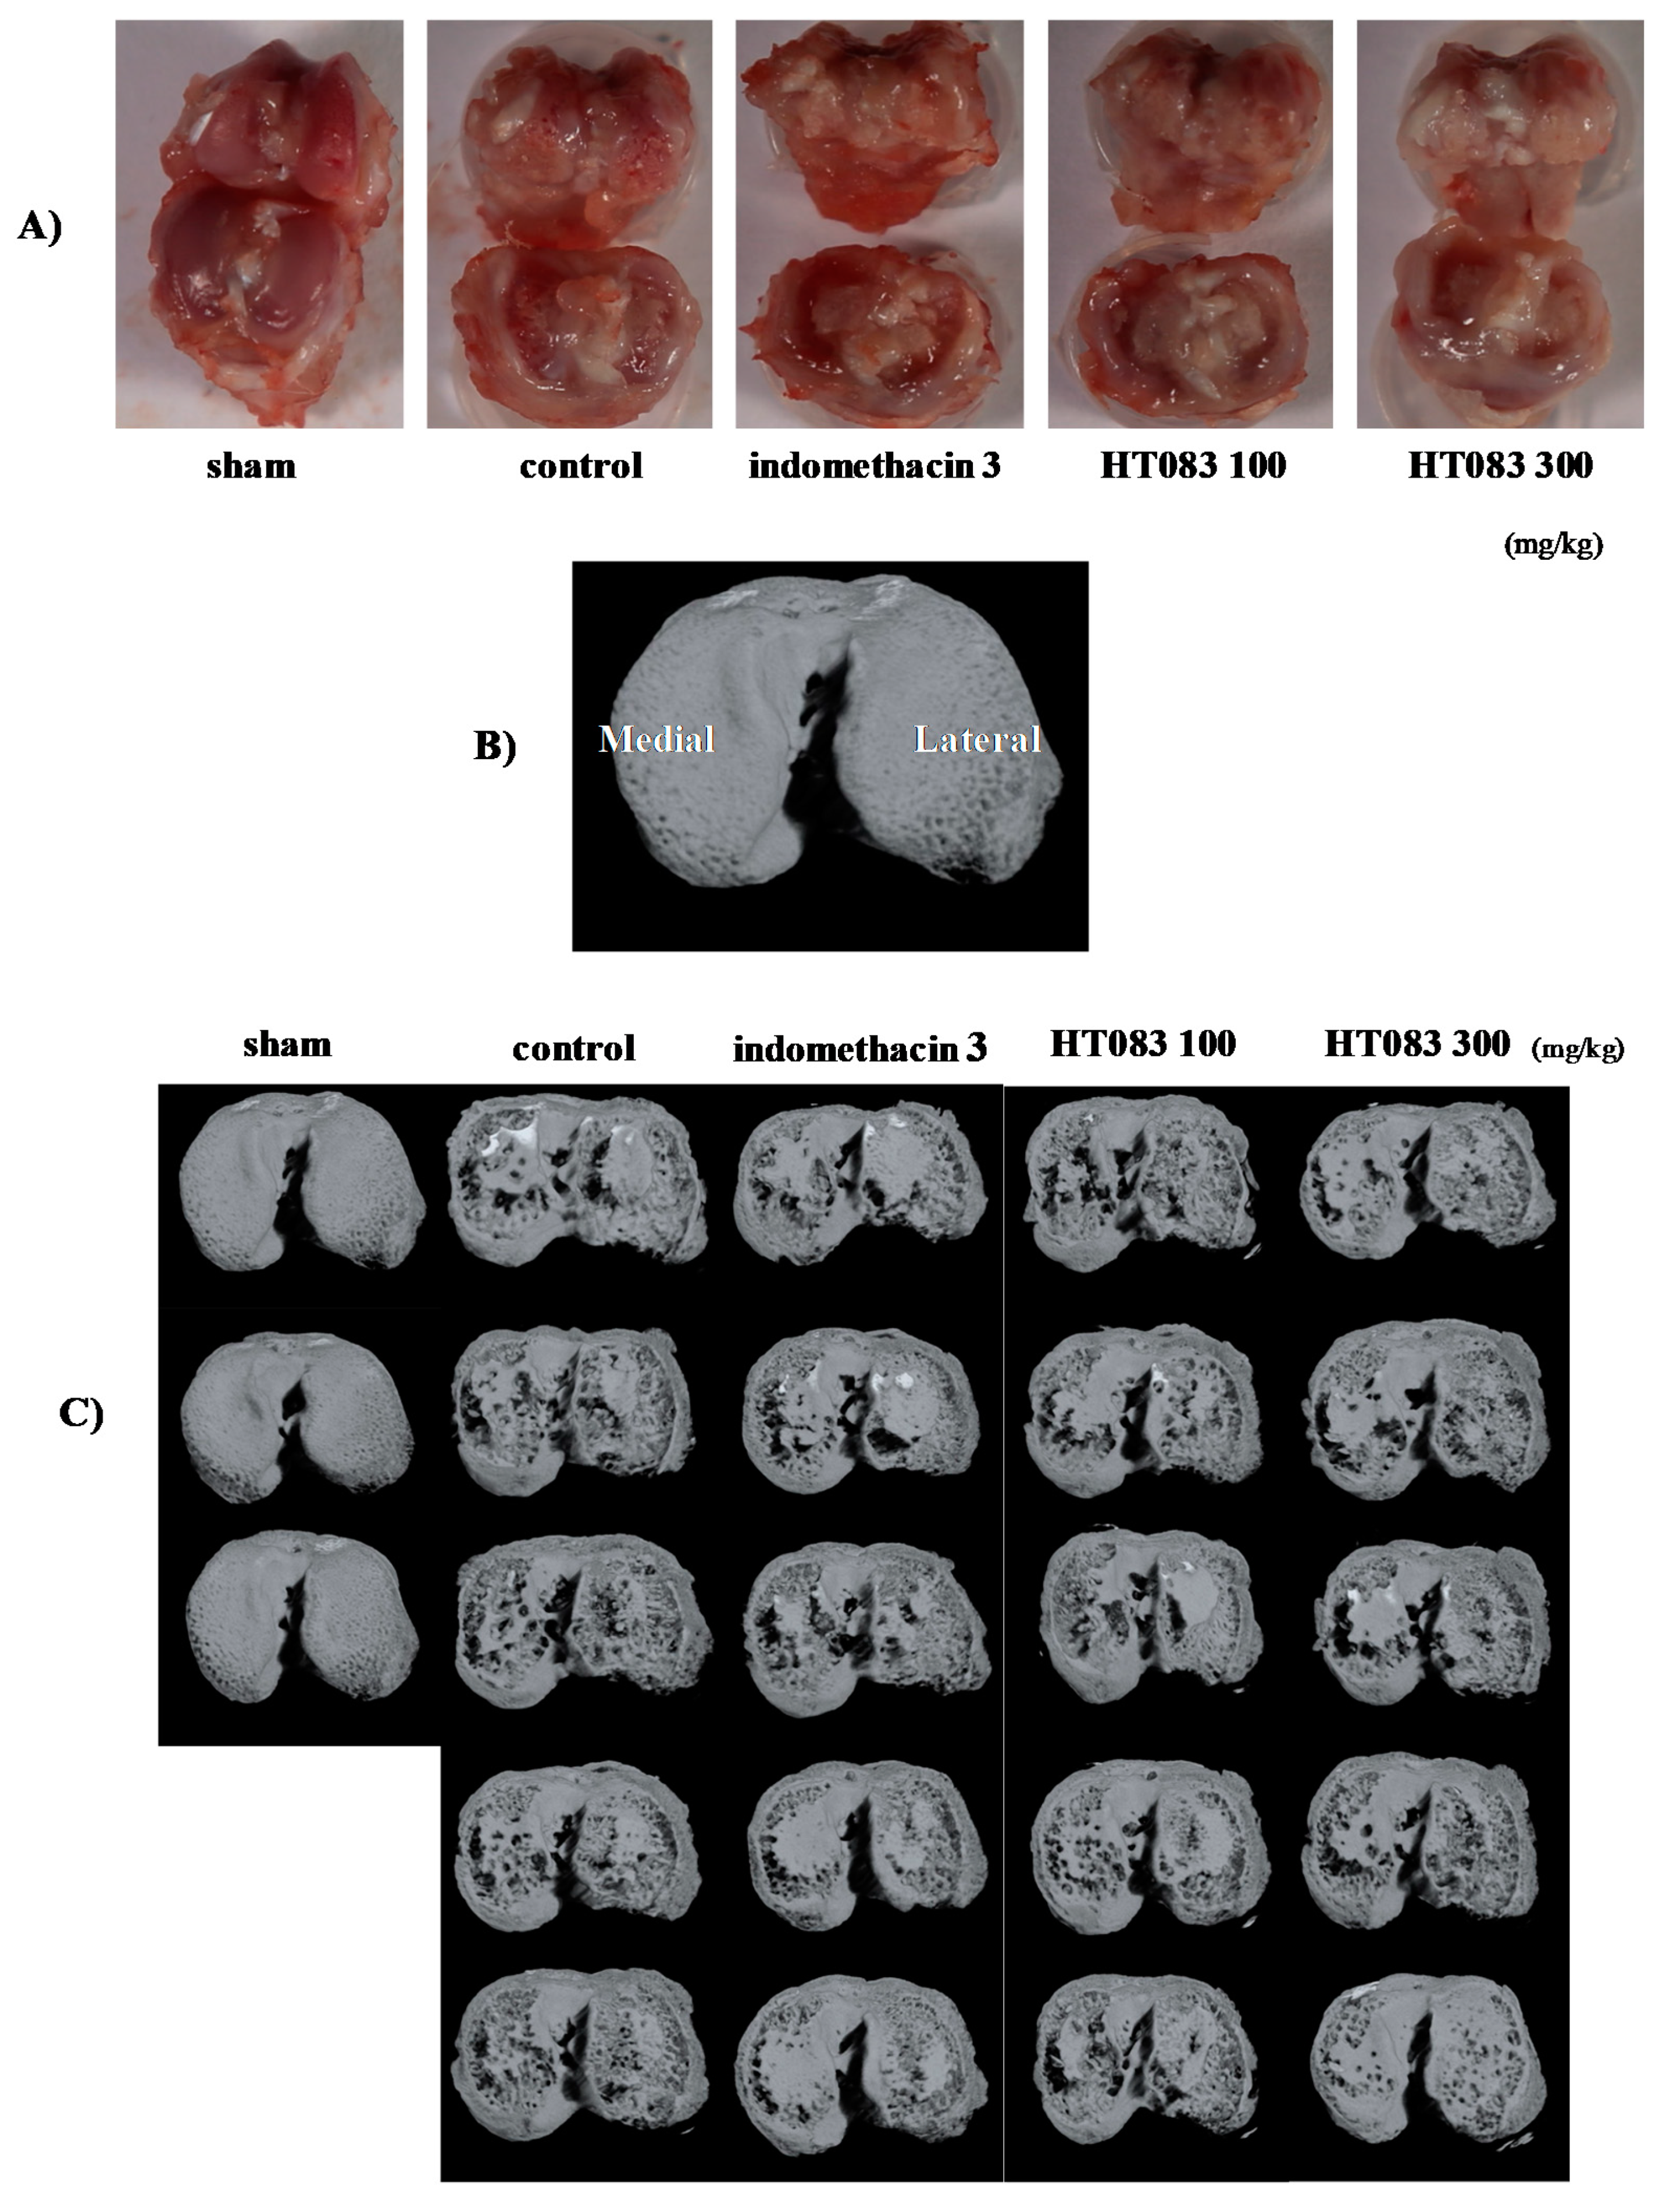

2.3. Knee Joints and Joint Cartilage by HT083

4.5. Micro-Computed Tomography (Micro-CT) Analysis